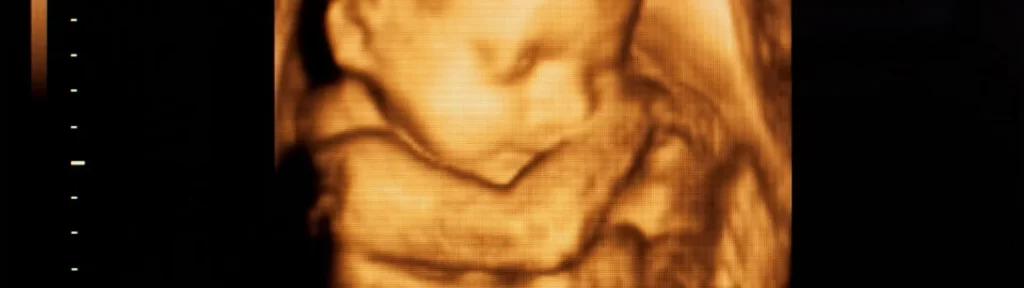

Nos anos 90, a tecnologia possibilitou o aumento da qualidade da imagem. O destaque era para as ultrassonografias em 3d e 4d, que permitiam a visualização e avaliação do feto.

Don Baker, Dennis Watkins, e John Reid em 1966 desenvolveram o Doppler pulsado, o que permitiu a detecção de fluxo de sangue a partir de diferentes profundidades no coração. Don Baker também era um membro da equipe de engenharia que desenvolveu mais tarde com Doppler colorido e digitalização duplex. Em tempo real de ultrassom começaram a aparecer no início de 1980. Já na década de 1990, o campo foi um passo adiante com imagens 3D e até 4D que o público poderia interpretar. Hoje, o exame ultrassonográfico acomoda-se confortavelmente ao paciente, onde o transdutor é o responsável por transformar os ecos refletidos pelo interior do corpo humano em sinais que serão decodificados eletronicamente em uma imagem que, por sua vez, será interpretada pelo médico que estiver realizando o exame.